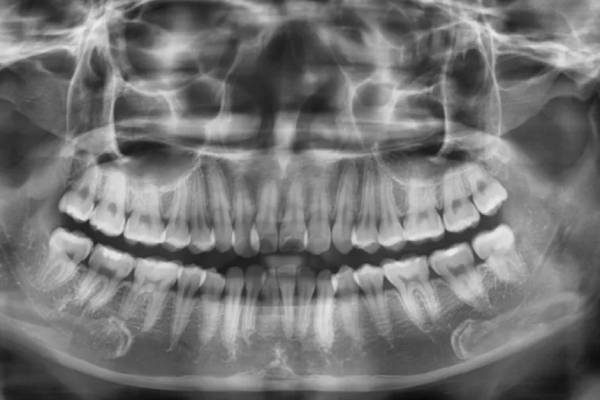

Trước tiên, bác sĩ sẽ tiến hành thăm khám cụ thể vùng cần trám và tiến hàng chụp X-quang cho người bệnh. Sau đó dựa vào kết quả kiểm tra để lên phác đồ điều trị phù hợp với từng bệnh nhân.